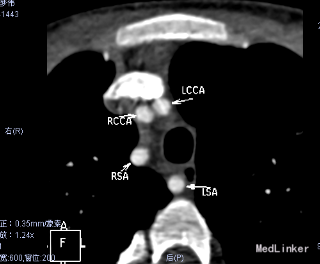

心脏CT:内脏、心房正位,左位心。肺动脉瓣二叶瓣,左室发育好。McGoon指数3.9。左室容积指数69.6ml/㎡。干下室间隔缺损,缺损约21.8mm。右位主动脉弓。迷走左锁骨下动脉。左锁骨下动脉异常起源于降主动脉起始处,经食管后方走行至左侧。左、右冠状动脉起源、走行未见异常。纵隔内未见体肺侧支动脉。气管下段中度狭窄。

患者因Fallot四联症行术前常规检查,发现合并迷走左锁骨下动脉。临床上迷走右锁骨下动脉比较多见。此患者右位主动脉弓。迷走左锁骨下动脉。左锁骨下动脉异常起源于降主动脉起始处,经食管后方走行至左侧。迷走左锁骨下动脉有二种类型:一种为单纯迷走锁骨下动脉,,一种同时合并Kommerell憩室。可能以22q11.2缺失有关。迷走左锁骨下动脉与双主动脉弓一样,是可以完整形成血管环的畸形。迷走左锁骨下动脉常合并有Fallot四联症、室间隔缺损等心脏畸形。心脏增强CT或核磁共振有助于左迷走锁骨下动脉诊断。通常没有食道、气管等脏器的压迫,不需要手术矫正。